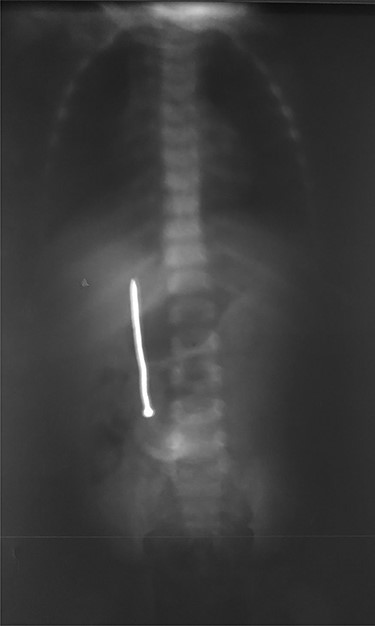

A 3-year-old male child was admitted in surgery department, with history of accidental ingestion of construction nail for 30 days, without any symptoms. Parents consulted in a peripheral hospital and plain abdominal radiography showed a nail projected in right-edge upon the lumbar spine (Fig. 1). Clinical observation was advised. The nail did not pass spontaneously and the child remained asymptomatic. Parents decided to consult again, but in our institution (surgery department). The child did not experience fever nor digestive symptoms (nausea, vomiting, abdominal pain, blood or color changes in stool). He had no prior history of FB ingestion.

Plain radiography plays the main role both in the diagnosis and the choice of operative interventional moment—either by pinpointing the radio-opaque image, or by showing certain FB characteristics, or by noting images suggesting complications (absent in our case), or even by projecting the FB in the same place over a period of time, an aspect inductive of fistula. In our case, right-edge superposition of the FB image upon the lumbar spine is characteristic of FB positioning in the second part of duodenum [5, 6]. Its persistence in the same place (the second part of the duodenum as in our case) suggests the presence of a duodenal fistula or perforation, which requires surgical intervention [7].